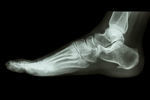

シーバー病/踵の痛み

【実例】シーバー病

1ヶ月経った頃、踵に痛みが起き始めます。

シーバー病と診断され6ヵ月間、踵の痛みは続いています。